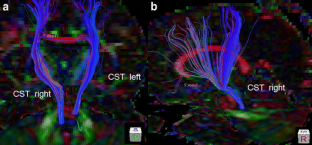

Fig. 2